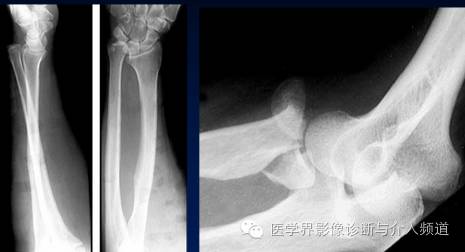

12、Nightstick 骨折

尺骨近端横形骨折。称“警棍骨折”,由直接暴力打击前臂造成。